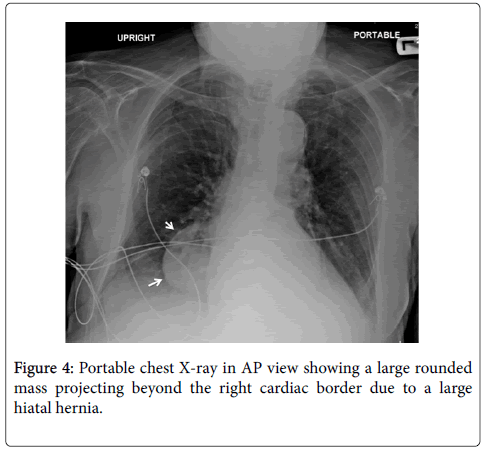

20+ Portable Ap Chest X Ray PNG. If you'd like to support us and get something great in return, check out our osce checklist booklet containing over 100 osce note if the film is ap or pa: This is usually because the patient is too unwell to stand.

The portable ap the portable exam is performed whenever the patient cannot come to the department for traditional pa and lateral radiographs of the chest. Even though healthcare providers portable cxrs should generally be reserved for acutely ill patients and others who can't stand. But, not to miss anything you should look at it in a systematic method.

An online course by lee herrington. 2 portable cxrs performed at the patient's bedside are ap views. You can find out detailed information and cxr examples on below mentioned categories. Reticulonodular opacities seen involving the left mid and lower zones.